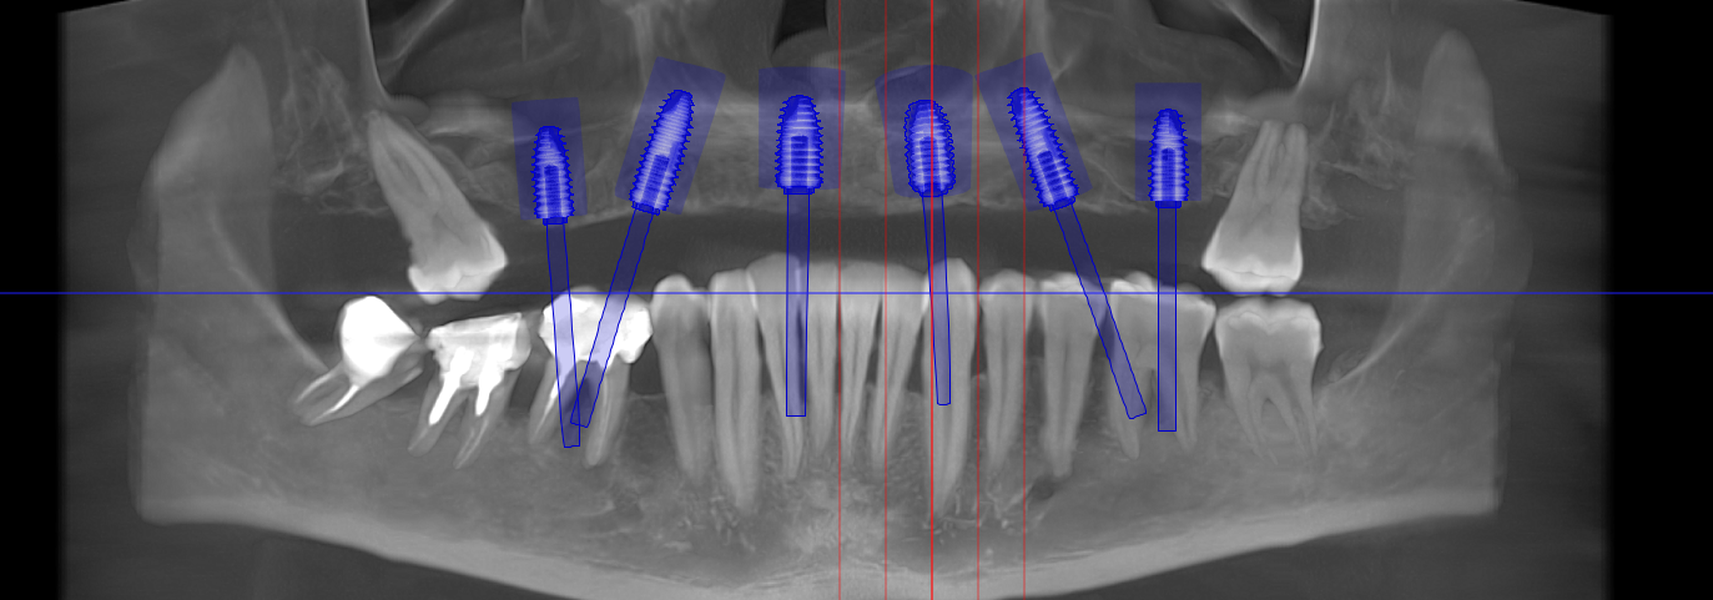

- Investigație imagistică completă, ideal CBCT (computer tomografie);

- Planificare computerizată a intervenției, inclusiv realizarea și utilizarea ghidului chirurgical, dacă este necesar;